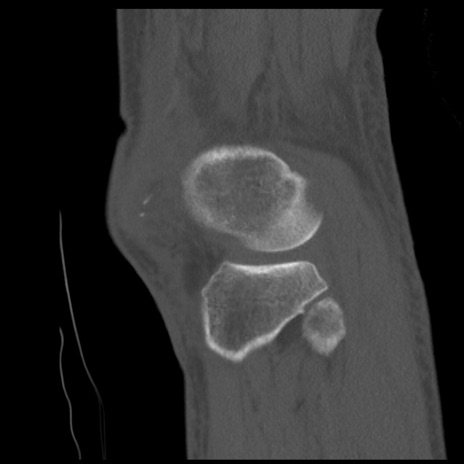

症例28 右膝関節CT(矢状断像)

右膝関節CT